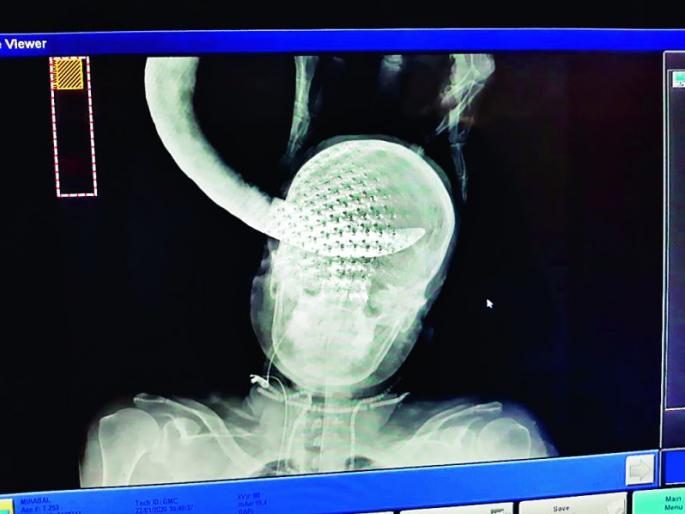

जोरदार वार केल्यामुळे एका ६५ वर्षीय महिलेच्या डोक्यात खोलवर रुतलेला विळा यशस्वी शस्त्रक्रिया करून बाहेर काढण्यात आला. शासकीय वैद्यकीय महाविद्यालय व रुग्णालय (मेडिकल) येथील ट्रॉमा सेंटरमध्ये गुरुवारी ही शस्त्रक्रिया पार पडली.

नागपूर : जोरदार वार केल्यामुळे एका ६५ वर्षीय महिलेच्या डोक्यात खोलवर रुतलेला विळा यशस्वी शस्त्रक्रिया करून बाहेर काढण्यात आला. शासकीय वैद्यकीय महाविद्यालय व रुग्णालय (मेडिकल) येथील ट्रॉमा सेंटरमध्ये गुरुवारी ही शस्त्रक्रिया पार पडली. त्यामुळे महिलेला जीवनदान मिळाले.

मीराबाई असे महिलेचे नाव असून त्या आसोली (पुसद, जि. यवतमाळ) येथील रहिवासी आहेत. अत्यंत गरीब असलेल्या मीराबाई रात्री घरात झोपलेल्या असताना अज्ञात इसमाने त्यांच्यावर विळ्याने जोरदार वार केला. तो विळा मीराबाईचा उजवा डोळा फोडून डोक्यात खोल रु तला. त्यानंतर त्यांना लगेच मेडिकलमध्ये हलविण्यात आले. मीराबाईची अवस्था पाहून ट्रॉमा सेंटरमधील डॉक्टर्स व परिचारिकांनी वेगात हालचाली केल्या. केवळ दीड तासामध्ये सर्व तपासण्या पूर्ण करून मीराबाईला शस्त्रक्रिया कक्षात हलविण्यात आले. त्यानंतर न्यूरोट्रॉमा विभाग प्रमुख डॉ. पवित्र पटनाईक यांच्या नेतृत्वातील चमूने अवघ्या एक तासात डोक्यात रुतलेला विळा सुरक्षितपणे बाहेर काढला. त्यानंतर फुटलेला डोळा बाहेर काढणे, जखम शिवणे यासह इतर आवश्यक उपचार करण्यात आले. या शस्त्रक्रियेमुळे मीराबाईला नवीन जीवन मिळाले.

मेंदूला धोका होता

ही शस्त्रक्रिया अत्यंत किचकट स्वरुपाची होती. या शस्त्रक्रियेमुळे मीराबाईच्या जीवाला धोका होता. विळा बाहेर काढताना मेंदूला कोणत्याही प्रकारची इजा पोहचणार नाही याची काळजी घेणे हे मोठे आव्हान होते. त्यात आम्ही यशस्वी ठरलो. मीराबाईला नवीन जीवन मिळाले याचा आम्हा सर्वांना आनंद आहे.

डॉ. पवित्र पटनाईक